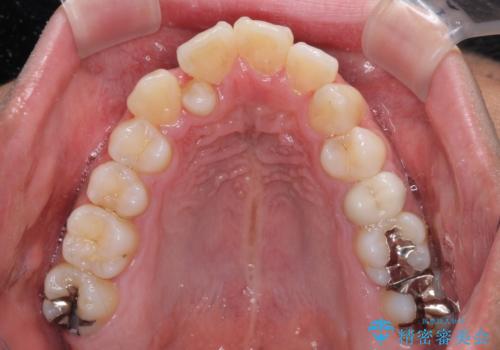

下顎の歯列弓に対して上顎歯列弓がやや小さく、側方の歯を中心にクロスバイトが見受けられました。

後方に隠れていた上顎前歯は矮小歯であるため、矯正治療の途中でオールセラミッククラウンを装着し、左右対称の大きさでの仕上がりを目指すこととしました。